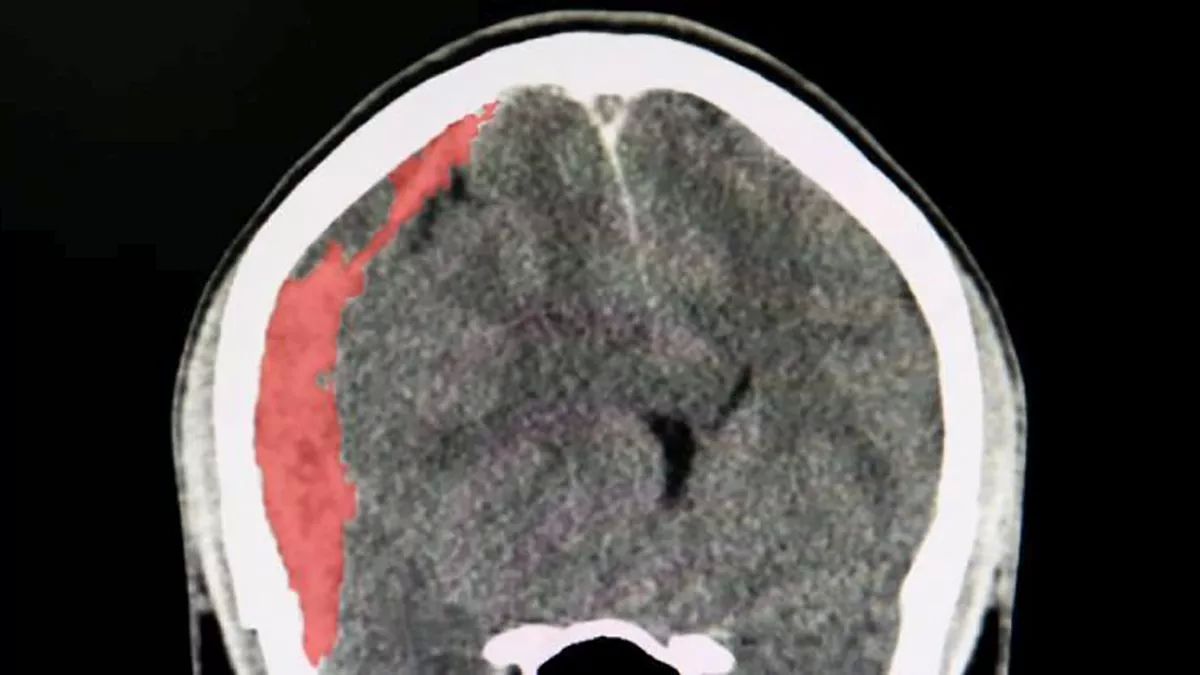

Pero ¿qué es exactamente un hematoma subdural y por qué es tan grave? Esta condición médica se presenta cuando se acumula sangre entre el cerebro y su cubierta externa, generalmente a raíz de una lesión en la cabeza. Los síntomas pueden ser sutiles al principio, pero sin tratamiento, puede llevar a complicaciones severas, incluso la muerte.

Existen dos tipos principales: el hematoma subdural agudo y el crónico. En el caso de Toriyama, se trata de una versión aguda, que es la más peligrosa y requiere atención médica inmediata. Este tipo de hematoma se desarrolla rápidamente después de un golpe fuerte en la cabeza, como los que pueden ocurrir en un accidente de tráfico o por una caída.